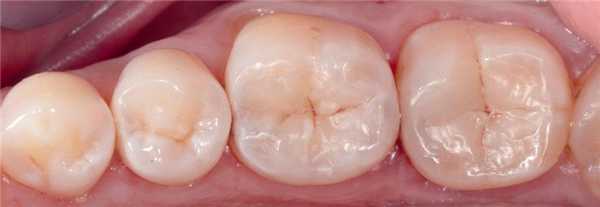

35-летняя пациентка обратилась за стоматологической помощью с просьбой заменить амальгамные реставрации в области первого и второго нижних молярах. Она также сообщала о наличие болезненных ощущений в проекции данных зубов при жевании. В ходе клинического осмотра были идентифицированы реставрации моляров, требующие срочной замены (фото 4). После удаления старых пломб и нанесения универсального адгезива Adhese Universal, объем дентина был восстановлен материалом Tetric EvoFlow Bulk Fill (фото 5). Данный композит обладает очень хорошими свойствами самовыравнивания и автоматически принимает вогнутую форму. В области второго моляра текучий композит вносили одновременно и на окклюзионную и на контактную поверхности. Полимеризацию обеспечивали лампой Bluephase (1200 мВт/см2) в течение 20 секунд. Производитель рекомендует обеспечивать полимеризацию композита на протяжении 10 секунд. Внесенная толщина слоя текучего композита не превышала 4 мм. Благодаря технологии Aessencio опаковость материала значительно увеличивается в процессе полимеризации (фото 5). Эмаль восстанавливали посредством материала Tetric EvoCeram A3, используя технику последовательного наращивания бугров. Фиссуры окрашивали при помощи IPS Empress Direct Color Brown (фото 6). Корректировку окклюзионных соотношений проводили после удаления коффердама. Поскольку бугорки изначально были смоделированы правильно, требовалась лишь минимальная окклюзионная коррекция, после которой приступили к полировке реставрации системой Astropol. Поверхности реставраций плавно сливались с окружающей структурой зуба (фото 7).

Фото 6. Восстановление эмали материалом Tetric EvoCeram A3 техникой последовательного наращивания бугров.

Фото 7. Вид после контурирования и полировки реставраций.

Тридцатилетний пациент обратился за стоматологической помощью по поводу дефектных реставраций двух нижних моляров (фото 8). После установки раббердама проводили удаление старых реставраций, под которыми был идентифицирован вторичный кариес (фото 9). Пораженный дентин удаляли твердосплавным бором на низких оборотах. После этого дополнительно проводили очистку полости методом воздушной абразии (частицами оксида алюминия размером 30 мкм). Редукцию щечного бугра первого моляра не проводили, поскольку он не подвергался значительным нагрузкам в процессе окклюзии и артикуляции (фото 10). Заполимеризированный текучий композит позволил добиться надлежащего перекрытия дисколорированных поверхностей дна отпрепарированных полостей (фото 11). Для восстановления эмали применяли IPS Empress Direct Enamel оттенка A2. Окрашивание фиссур проводило IPS Empress Direct Color. Готовые и отполированные реставрации визуально не отличались от естественной структуры зуба (фото 12).

Фото 12. Вид после контурирования и полировки реставраций.